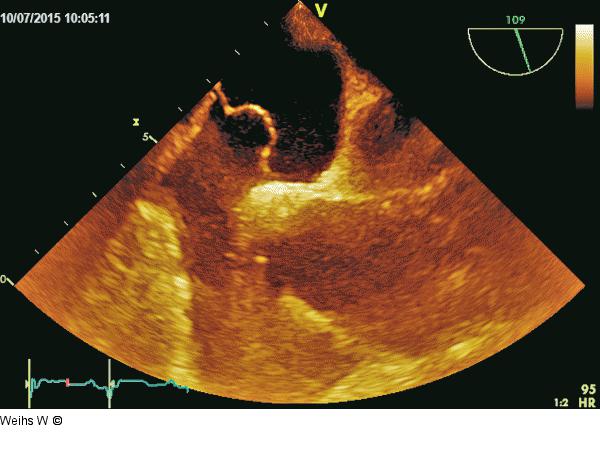

Abbildung 1: Vorhofseptumaneurysma Mobiles Vorhofseptumaneurysma mit kleinem PFO. |

Mobiles Vorhofseptumaneurysma mit kleinem PFO. |